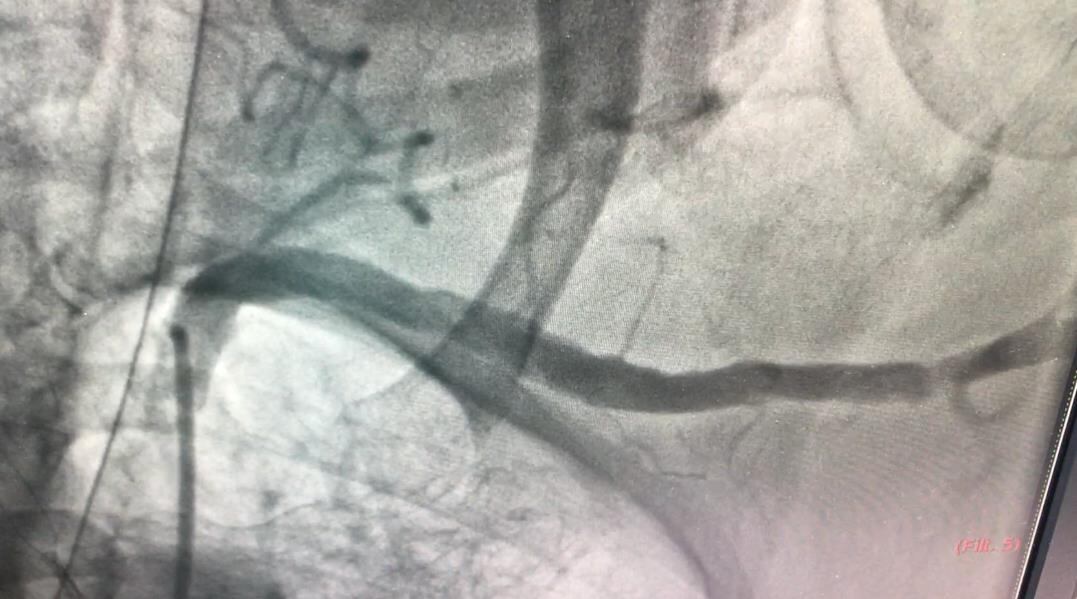

Al finalizar la intervención, los médicos hicieron una angiografía de la arteria axilar para así corroborar el adecuado cierre del sitio de acceso y verificar que no había complicaciones.